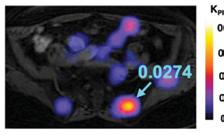

In the 2020-21 issue of Images, we shared the story of the U.S. Food and Drug Administration’s approval of Prostate-Specific Membrane Antigen (PSMA) PET imaging, based on research conducted at UC San Francisco and UCLA. The technique uses positron emission tomography in conjunction with a PET-sensitive drug that is highly effective in detecting prostate cancer throughout the body so that it can be better and more selectively treated. The PSMA PET scan also identifies cancer that is often missed by current standard-of-care imaging techniques.

At this time, UCSF and UCLA are the only two medical centers in the U.S. that can offer PSMA PET to the public through this FDA approval. A limited number of other U.S. medical centers are currently using PSMA as an investigational technique, generally as part of a clinical trial. However, more hospitals will have the opportunity to adopt the technology in 2022 after applying for expedited FDA approval, which is now possible as a result of the initial FDA approval gained by UCLA and UCSF.

In September 2021, a team led by Thomas Hope, MD, at UCSF and Jeremie Calais, MD, at UCLA, published a paper in JAMA Oncology (doi:10.1001/ jamaoncol.2021.3771) detailing the phase 3 diagnostic efficacy trial that led to FDA approval of PSMA PET.

What is the main focus of the JAMA Oncology paper?

The paper focuses on the role of 68Ga-PSMA-11 PET at time of initial staging. The goal was to compare the imaging results to nodes found at time of surgery in order to determine the sensitivity and specificity of PSMA PET. This study showed that PSMA PET has a high specificity for the detection of nodal metastases, although the sensitivity for small pelvic nodes was lower than expected.

What’s next for PSMA PET imaging?

Next up is to grow the use of PSMA PET for patient selection in PSMA radioligand therapy.

Currently there are no FDA approved agents for PSMA radioligand therapy, but we expect approval of 177Lu-PSMA-617 in the coming months, and so we will start using PSMA PET in this patient population.  Additionally, now that PSMA PET will be widely available, we will need to complete clinical trials in order to understand how to manage patients better based on the results of PSMA PET imaging studies. 